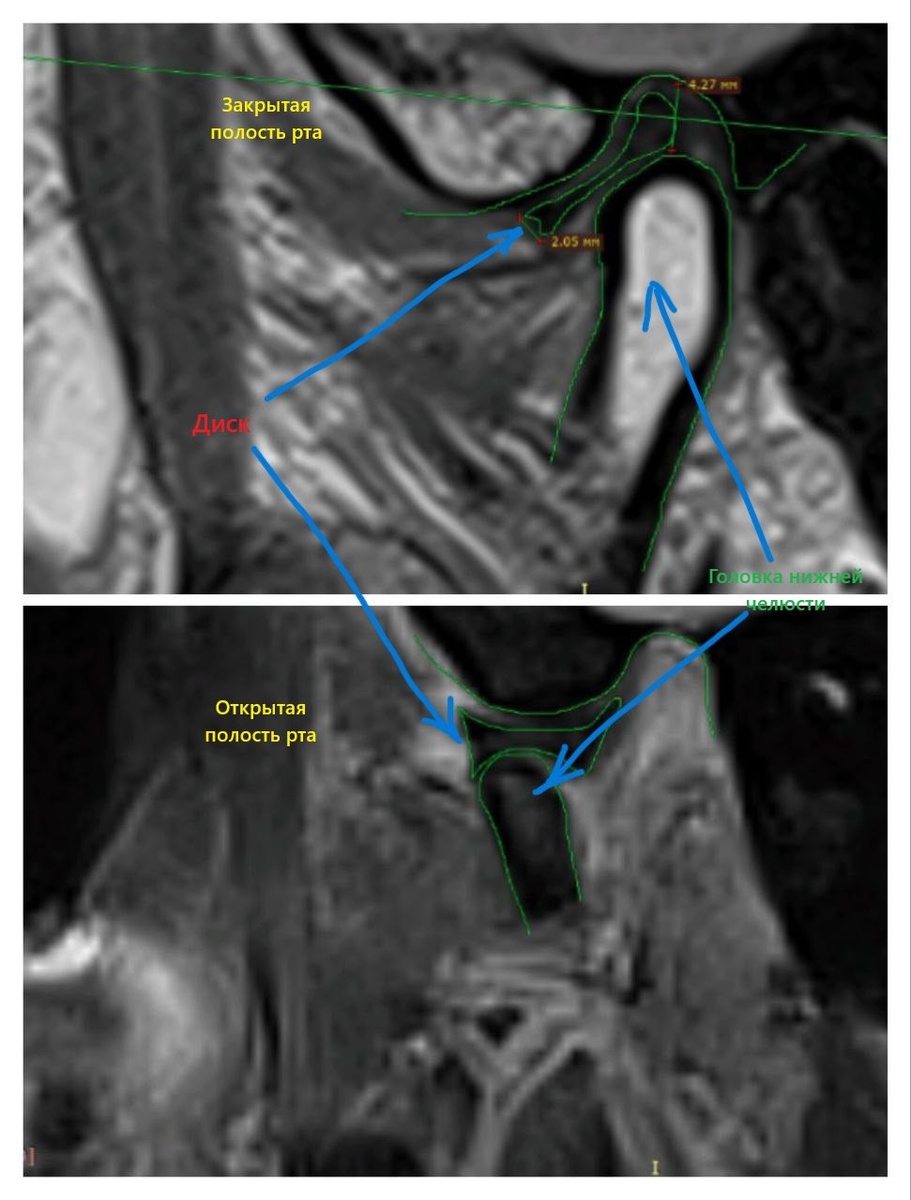

Друзья, сегодня хочу показать дисфункцию внчс на мрт📍 1 коллаж правая сторона: на которой имеются изменения, Суставной диск смещен кпереди, задний край на 9 ч.у.ц., МР-сигнал от него неоднородный, за счет дегенеративных изменений. При открывании рта суставной диск полностью смещен кпереди от головки нижней челюсти. Структурность волокон биламинарной зоны сохранена. 2 коллаж левая сторона: Суставной диск не смещен в передне-заднем направлении, в корональной плоскости не смещен, МР-сигнал от него При открывании рта суставной диск занимает нормальное положение, расположен междусуставными поверхностями.

1 коллаж правая сторона: на которой имеются изменения, Суставной диск смещен кпереди, задний край на 9 ч.у.ц., МР-сигнал от него неоднородный, за

счет дегенеративных изменений.

При открывании рта суставной диск полностью смещен кпереди от головки нижней челюсти.

Структурность волокон биламинарной зоны сохранена.